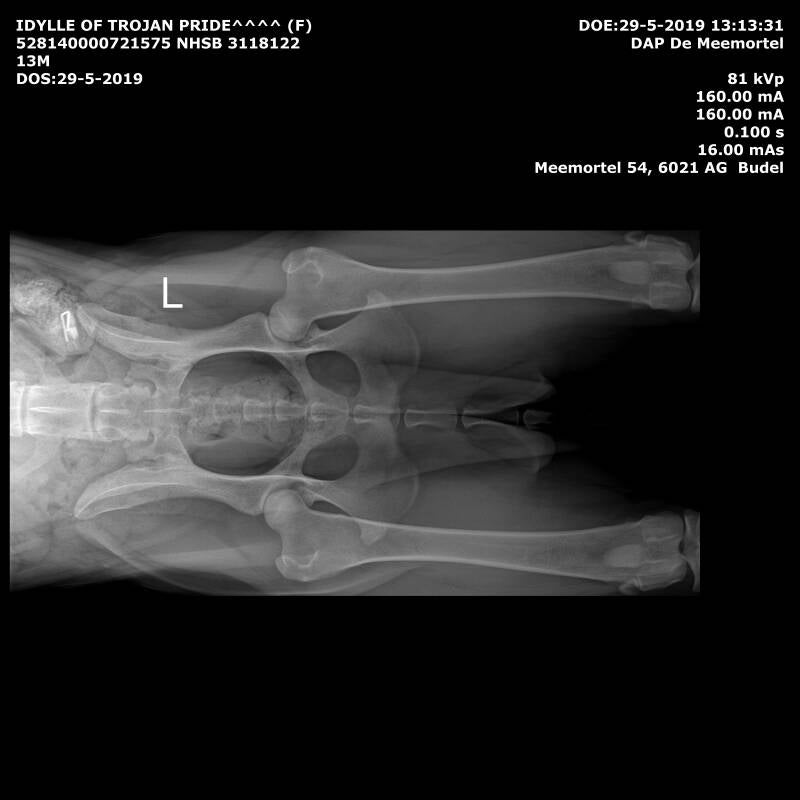

Uitslagen: testen: Hd A